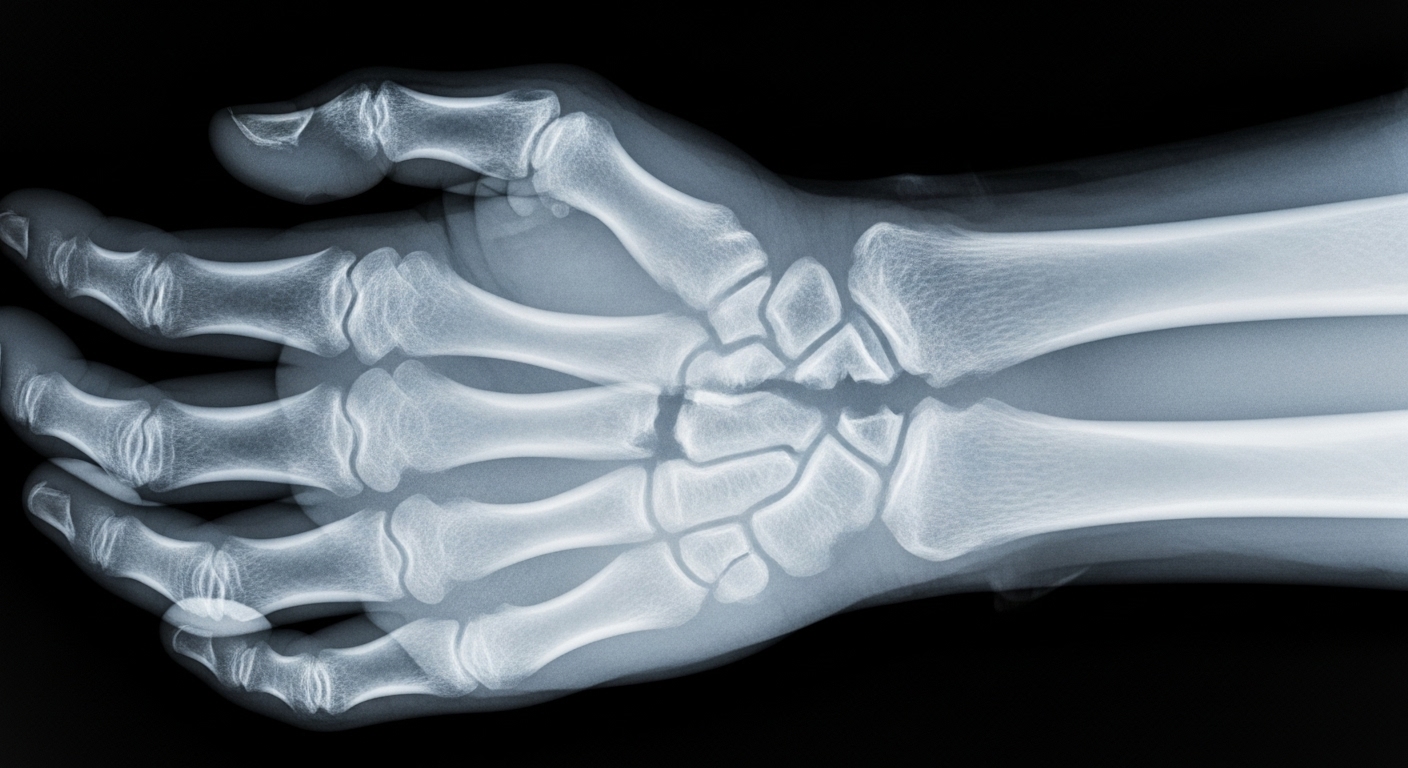

뼈가 약해지면 손가락과 같이 비교적 작은 충격에도 쉽게 부러질 수 있습니다. 일상생활 속에서의 사소한 넘어짐이나 가벼운 부딪힘이 골다공증 환자에게는 매우 치명적인 결과를 가져올 수 있다는 점을 항상 경계해야 합니다.